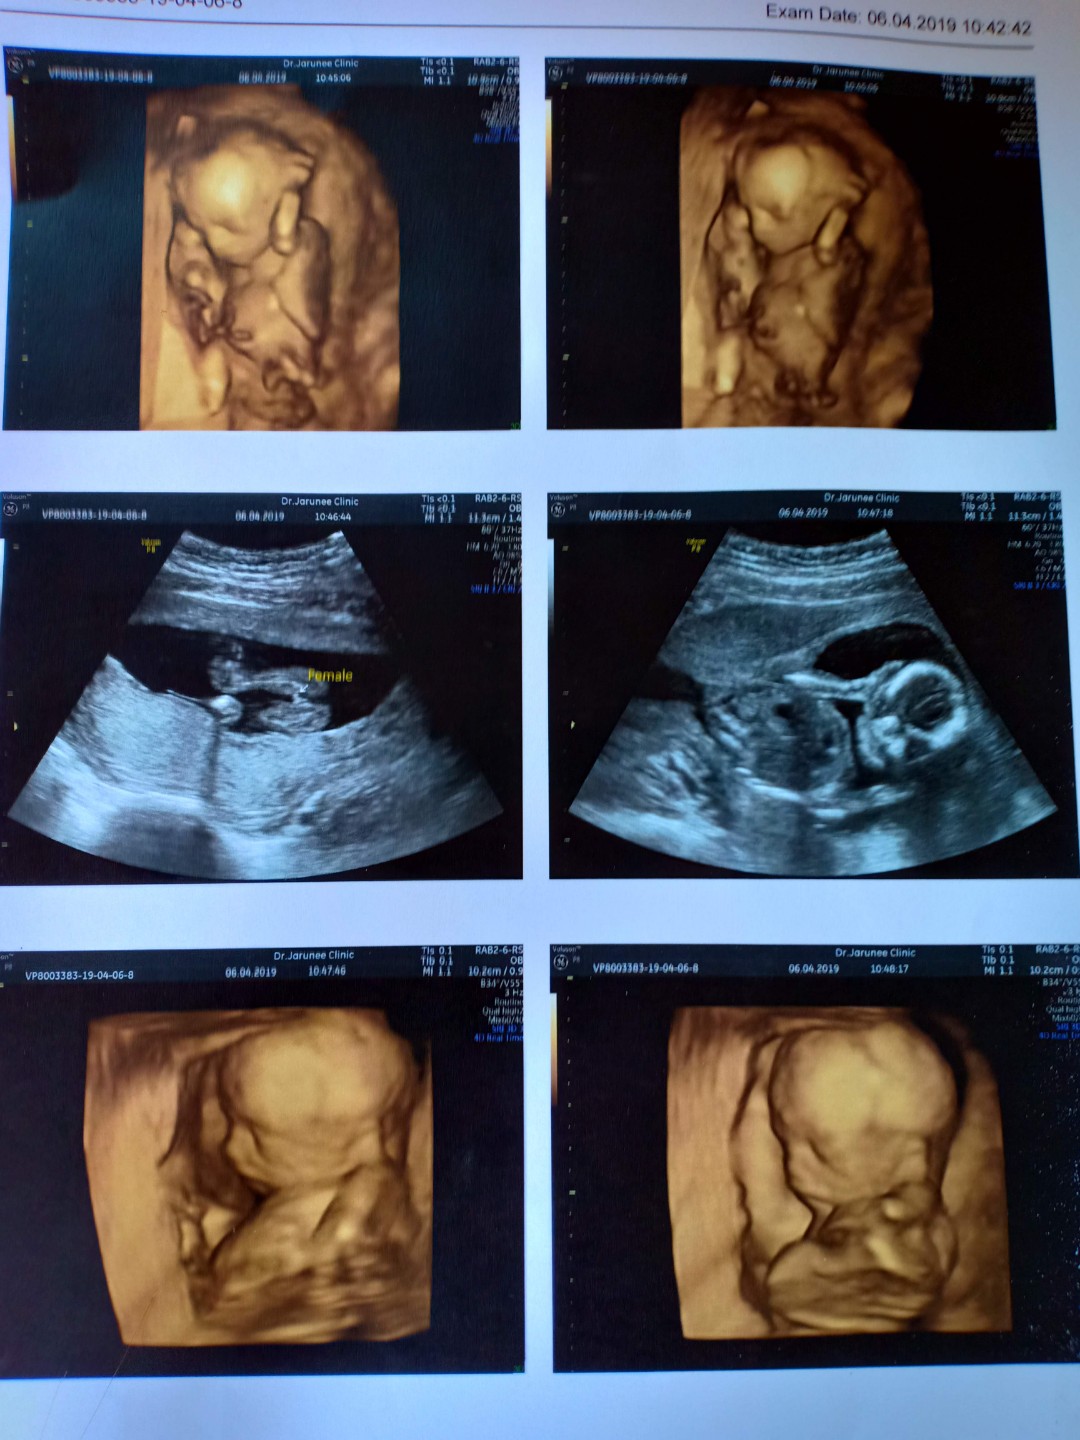

แก้มป่องๆ❤️รูปตอน27วีคจ้า ตอนนี้ 33วีคแล้วจ้า